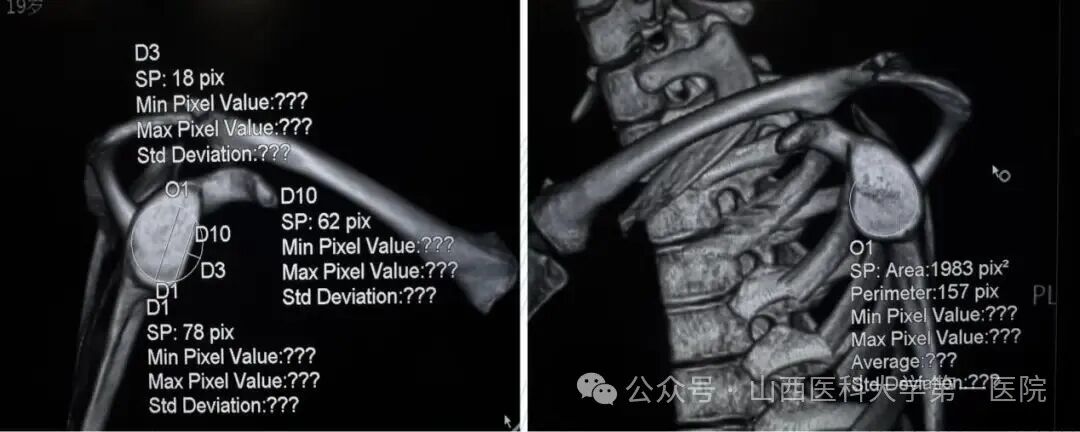

术后CT三维重建:关节盂前下完美覆盖